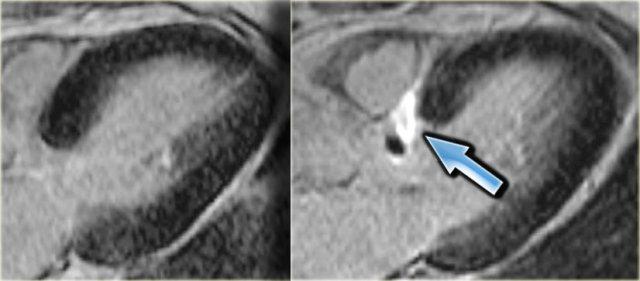

Trái: hiện tượng không tái tưới máu, Phải: bốn tháng sau có ngấm thuốc xuyên thành cho thấy nhồi máu xuyên thành

Hiện tượng không tái tưới máu (No-reflow)

Hiện tượng không tái tưới máu là tình trạng máu không thể tưới lại vùng thiếu máu sau khi tắc nghẽn cơ học đã được giải phóng hoặc bắc cầu.

Các vùng không tái tưới máu được xác định trên ảnh ngấm thuốc muộn dưới dạng vùng lõi giảm tín hiệu được bao quanh bởi viền ngấm thuốc.

Hình ảnh này cho thấy sự hiện diện của tổn thương vi mạch tại vùng lõi của ổ nhồi máu.

Sự hiện diện của vùng ‘không tái tưới máu’ có liên quan đến tiên lượng chức năng xấu hơn, diện tích nhồi máu lớn hơn và kết cục lâm sàng bất lợi [8,9].

Cả nhồi máu cấp tính và mạn tính đều biểu hiện ngấm thuốc muộn, tuy nhiên nhồi máu cấp tính thường có thể được phân biệt bởi sự hiện diện của vùng ‘không tái tưới máu’ và tăng tín hiệu trên ảnh chuỗi xung T2W.